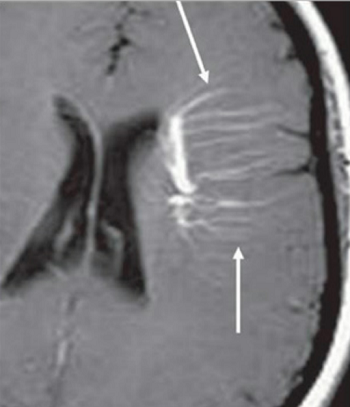

Medusa Head Sign

Differentials

Developmental venous anomaly